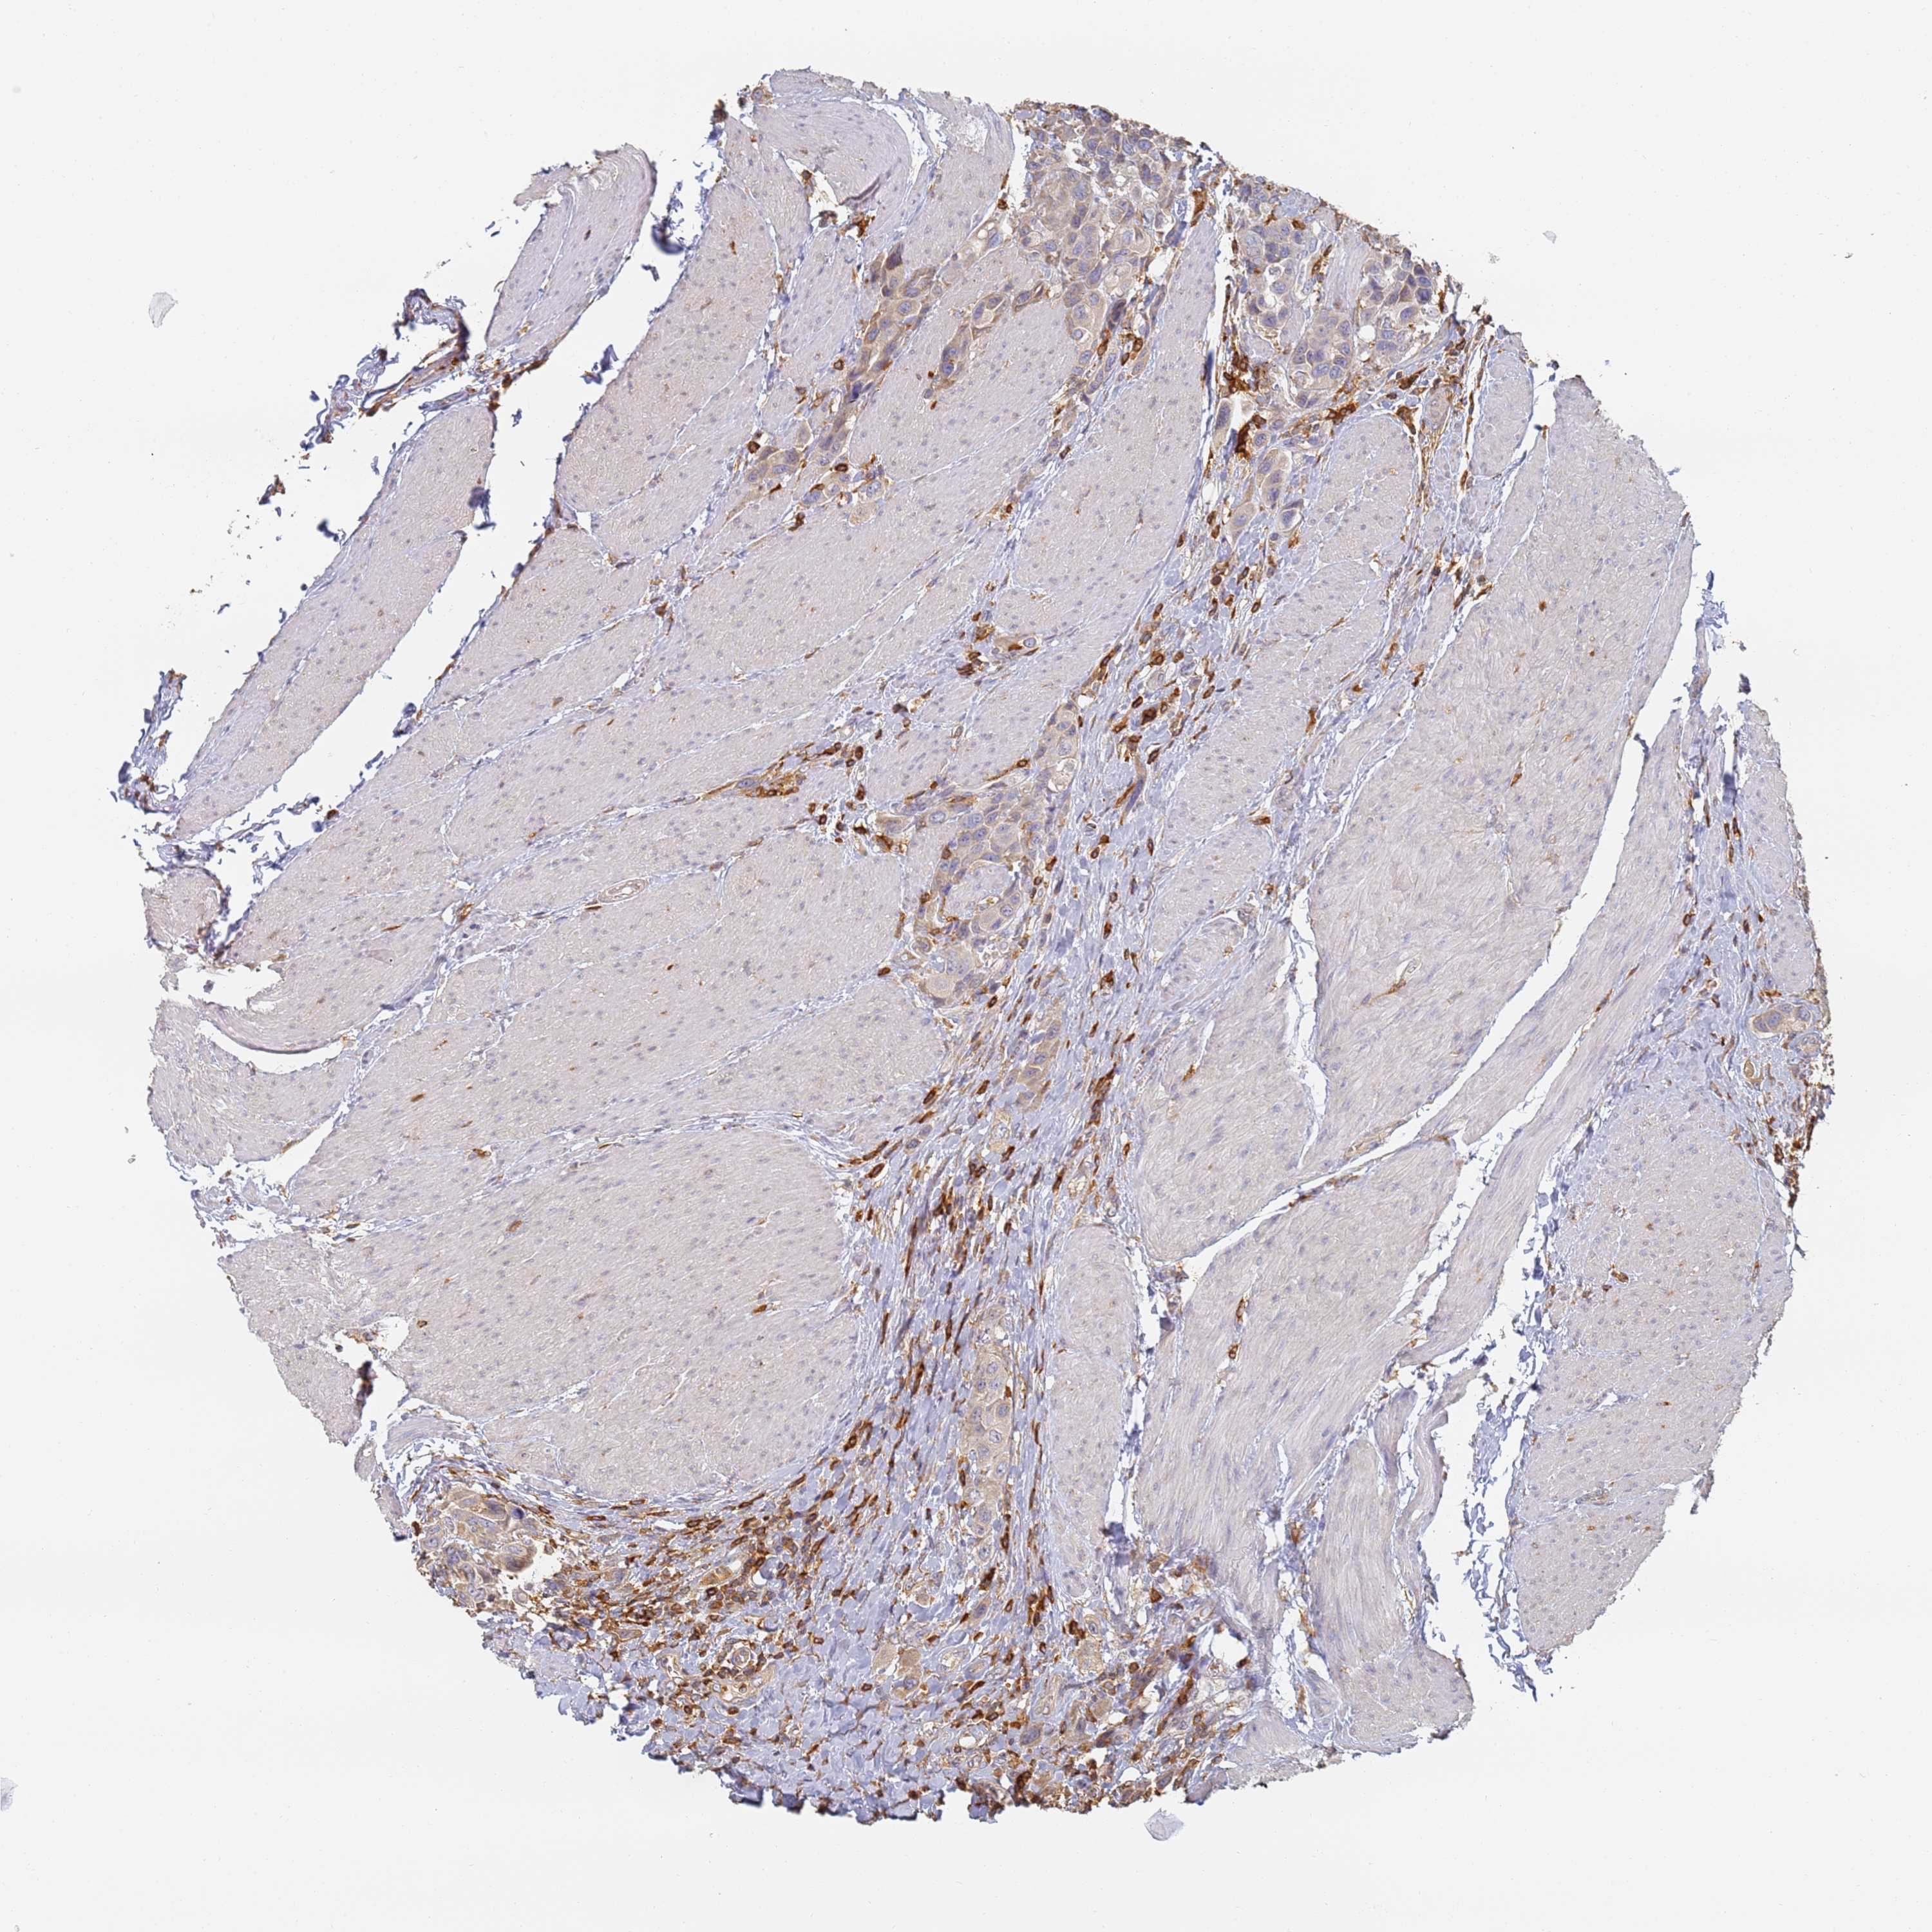

UROTHELIAL CANCER - Protein expressioni

A mouse-over function shows sample information and annotation data. Click on an image to view it in a full screen mode. Samples can be filtered based on level of antibody staining by selecting one or several of the following categories: high, medium, low and not detected. The assay and annotation is described here.

Note that samples used for immunohistochemistry by the Human Protein Atlas do not correspond to samples in the TCGA dataset.

Antibody stainingi

Antibody staining in the annotated cell types in the current human tissue is reported as not detected, low, medium, or high, based on conventional immunohistochemistry profiling in selected tissues. This score is based on the combination of the staining intensity and fraction of stained cells.

Each image is clickable and will lead to virtual microscopy that enables deeper exploration of all samples and also displays staining intensity scores, fraction scores and subcellular localization as well as patient and tissue information for each sample.

Antibody HPA038666

Antibody HPA038667

Urothelial carcinoma, High grade

Urothelial carcinoma, Low grade